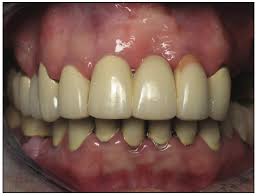

Full Mouth Reconstruction